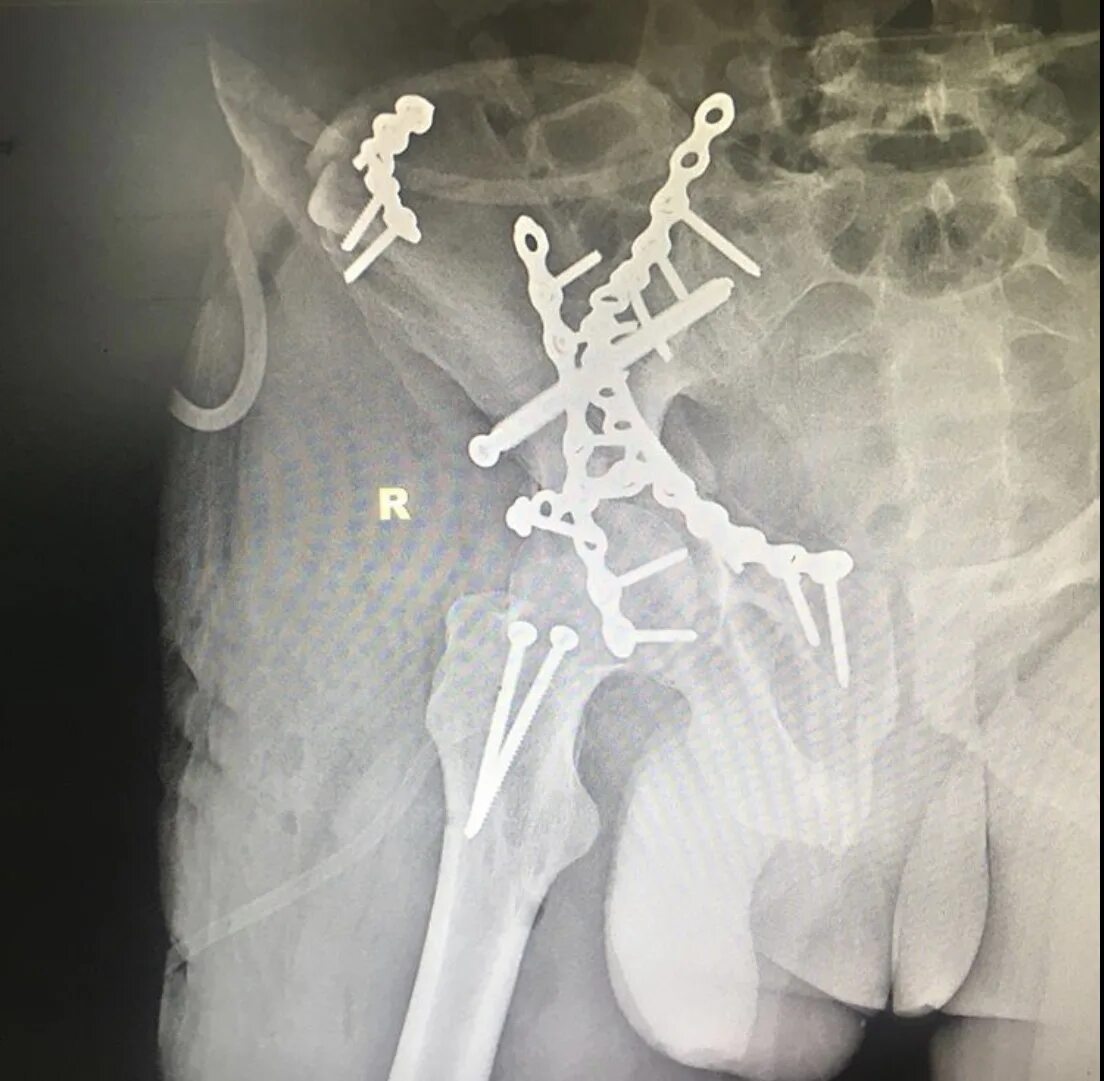

Перелом тазобедренной впадины